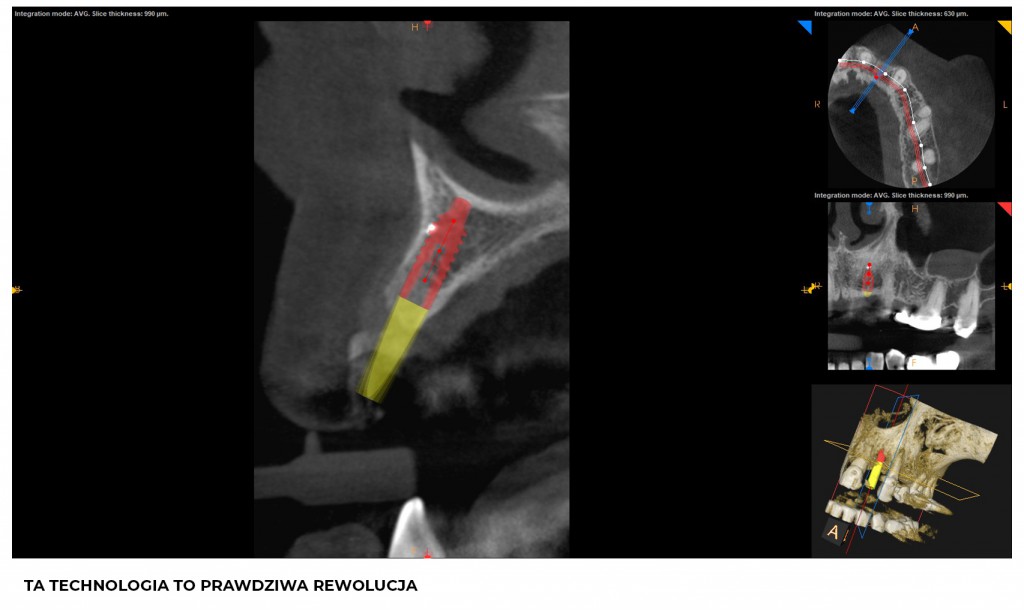

Pozycjonowanie implantów zębowych do niedawna uzależnione było wyłącznie od wiedzy, doświadczenia i chirurgicznej intuicji implantologa. Technologia CAD-CAM otworzyła wrota świadomej i bezpiecznej chirurgii szczepowej. Szablon chirurgiczny powstaje w drodze nałożenia obrazu otrzymanego dzięki skanowaniu z obrazem z CBCT (tomografia). Lekarz otrzymuje precyzyjny i rzeczywisty obraz tkanek w obrębie jamy ustnej pacjenta. Na tej podstawie ocenia ilość, gęstość i wymiary wyrostka zębodołowego oraz biotyp tkanki miękkiej, aby dostosować idealny kształt i rozmiar implantów.